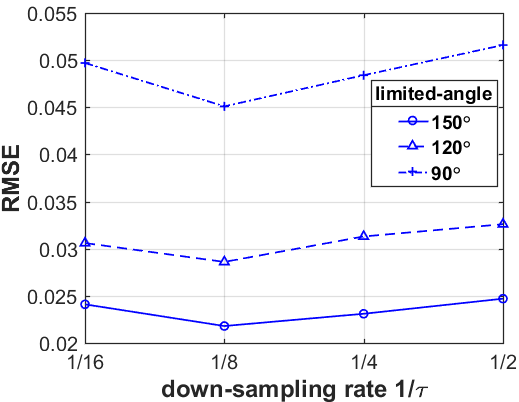

What is more, as shown in Table III, IV and V, the smaller the down-sampling rate, the better the reconstruction result. Since the quality of the image prior decreases as the resolution decreases for the limited-angle reconstruction problems, there is a trade-off between the resolution and the quality. Thus, we track the relationship between the resolution of the low-resolution image priors and the performance of our LRIP-net. As shown in Fig. 9, the best reconstruction results are obtained using the low-resolution image prior with down-sampling rate . Although the smaller the condition number of the system matrix, the better the numerical stability of the solution, it does not mean that the better the performance of our LRIP-net.